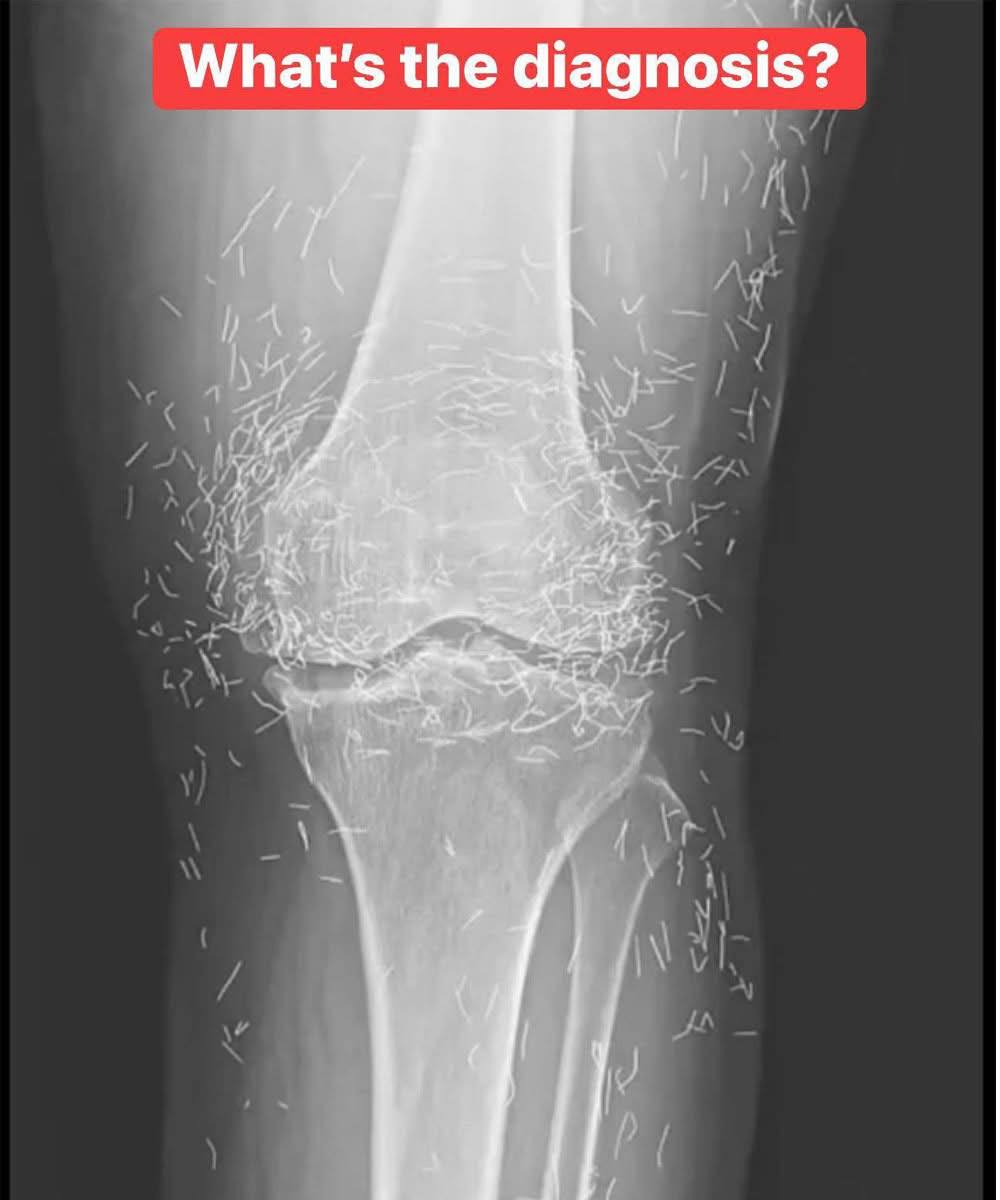

A 65-year-old woman came to the clinic after experiencing months of chronic knee pain. Despite trying multiple treatments including traditional Chinese medicine she found no relief. This X-ray was taken during her visit. What do you think is the diagnosis? 🦴

A 65-year-old woman in South Korea discovered the surprising cause of her chronic knee pain:…